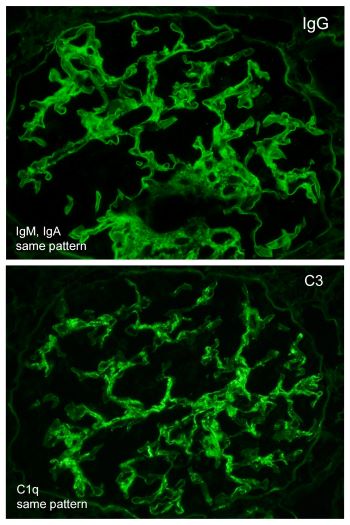

A 42-year-old African-American female with a history of systemic lupus erythematosus with acute kidney injury (creatinine 2.7 mg/dL), proteinuria (1064 mg/24 hr), and no hematuria, was admitted for lupus encephalitis. Renal biopsy by light microscopy showed that most glomeruli had no lesions (Figure 1) with one glomerulus with glomerular tuft collapse, and podocyte hypertrophy/hyperplasia (Figure 2). There was positive mesangial staining by immunofluorescence with IgG, IgM, IgA, C3, C1q, and light chains (Figure 3). Electron microscopy findings included diffuse foot process effacement, and mesangial electron-dense deposits (Figure 4).